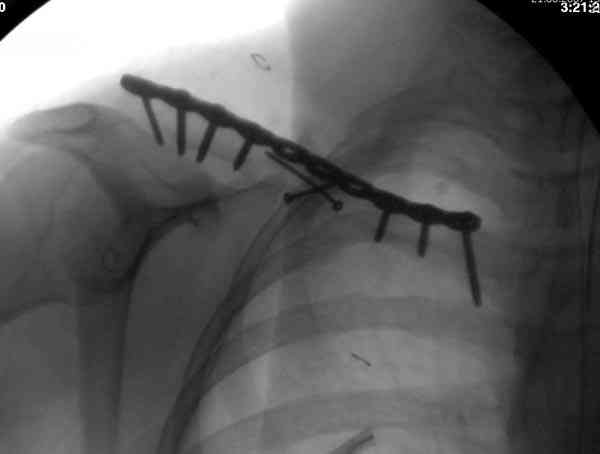

Re: Ортопедический квест: <допустимое> смещение от

Второй случай тоже недавно оперирован по поводу

ложного сустава, в марте травма, через 4.5 половиной

операция..

Djoldas Kuldjanov, MD